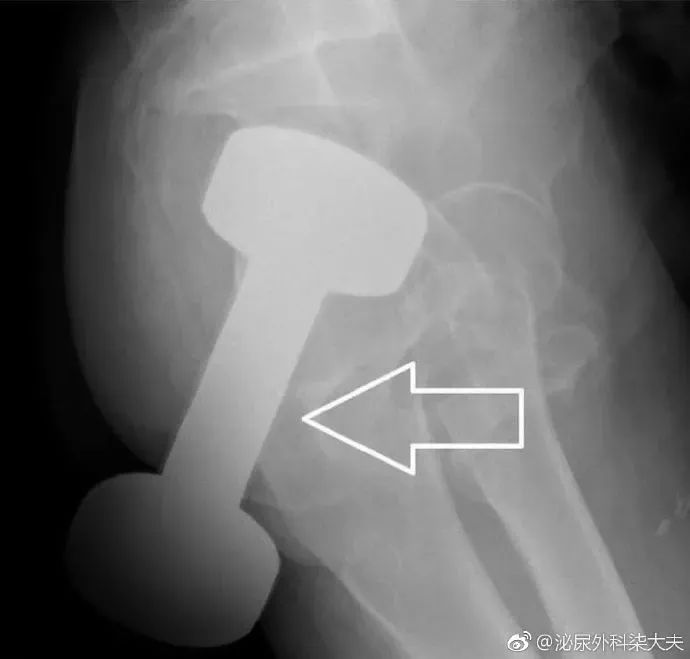

医生会通过一系列检查如直肠指诊、X线来确定体内的异物是什么,在什么位置,这一点非常关键,因为只有搞清楚里面的真实情况,医生才能找到合适的方法把异物取出。 一些小的、圆的异物,像小跳蛋、玻璃球,一般可以自行排出。 如果不行的话就需要在腰麻等麻醉下充分扩肛后取出,对于果壳、鱼刺与粪便结成的大团块,可灌入石蜡油后用卵圆钳夹碎,分块取出。

这一招还不行的话,可以采取剖腹探查术,打开腹腔,探查异物在肠道里的位置,一边挤压肠子,一边从肛门取异物。 如果上述方法都不管用,那就需要切开肠子取出异物,这是医生和患者最不愿意看到的。 无论是意外还是“一不小心”,直肠异物都是一件让人尴尬羞于开口的事情,但它背后的健康风险不容忽视。如果真的要“玩”,一定要保证安全,如果一不小心发生了意外,一定要及时就医!